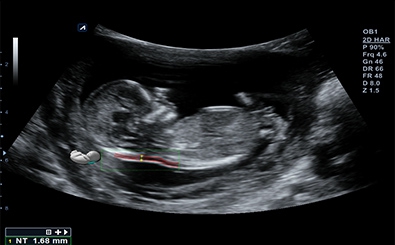

Auto NT